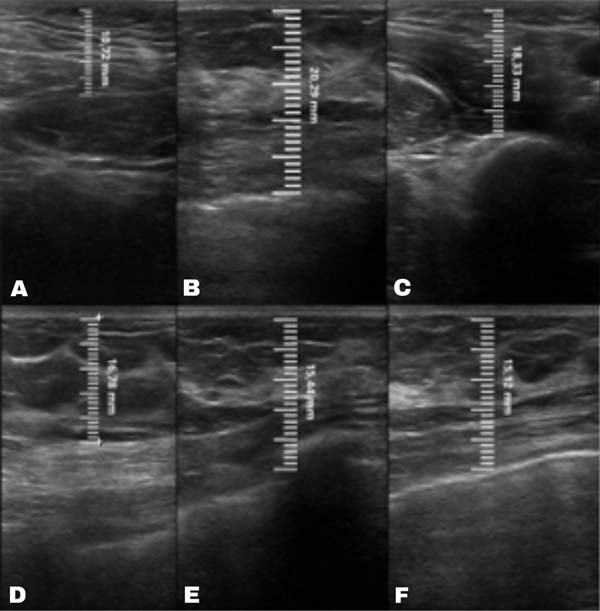

A mensuração da espessura do tecido subcutâneo é realizada de forma vertical, do ponto mais alto (logo na transição da epiderme) ao ponto mais baixo (na transição com o tecido muscular) da espessura de tecido subcutâneo. Essa medida é de fácil reprodutibilidade para quem possui aptidões básicas em ultrassonografia. ►Fig. 2. A medida da espessura de tecido subcutaneo na mama lipoenxertada foi realizada no pré- e pós-operatório imediato da lipoenxertia, e após 15,30, 90 e 180 dias. As medidas foram feitas atraves da ultrassonografia, em milimetros, medindo a distancia vertical do ponto mais superior (proximo à epiderme) ao mais inferior (proximo à musculatura adjacente) do tecido subcuta neo no ponto previamente definido. Foi utilizado equipamento de ultrassom modelo GE, LOGIQP6 (GE Healthcare) com uso de sonda linear de 11L com faixa de frequencia de 12 a 6 MHz, operado por cirurgião com pós graduação lato sensu em ultrassonografia geral. ►Fig. 3.

No grupo enxerto decantado, a reducãomédia, comparando-se a espessura inicial apos lipoenxertia, foi de 9,90% no 15° dia, 19,27% no 1° mes, 23,59% no 3° mes e 26,36% no 6° mes. No grupo enxerto filtrado, a reducao media, comparando-se a espessura inicial apos lipoenxertia, foi de 7,74% no 15° dia, 14,85% no 1° mes, 20,67% no 3° mes e 22,80% no 6° mes. ►Fig. 6. A evolução ao ultrassom da espessura do tecido subcutâneo antes e depois da lipoenxertia pode ser vista nas ►Figs. 7-8. Os resultados de pré-e pós-operatório de uma paciente de cada um dos grupos estão exibidos nas ►Figs. 9-10.